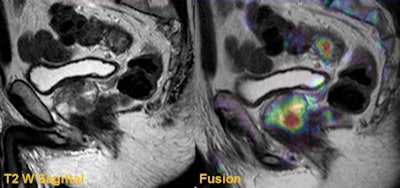

It is difficult to confidently delineate the local invasion of this low rectal tumor on the axial T2-weighted image. The DWI fusion image not only outlines the tumor but also defines its invasion through the muscularis. All images courtesy of Dr. Arun Jacob and Dr. Muthukumarasamy Balasubramaniam.

Sagittal T2-weighted and fusion images from a rectal staging examination show an upper rectal tumor. Fusion images also identified a clinically significant prostate cancer that had a significant impact in radiotherapy and treatment planning.It's vital to understand the additional value of DWI in rectal cancer imaging, given the technique's usefulness in tumor detection, tumor characterization, tumor staging, predicting and evaluating tumor response to preoperative chemoradiotherapy, tumor surveillance, and extracolonic findings, he added.